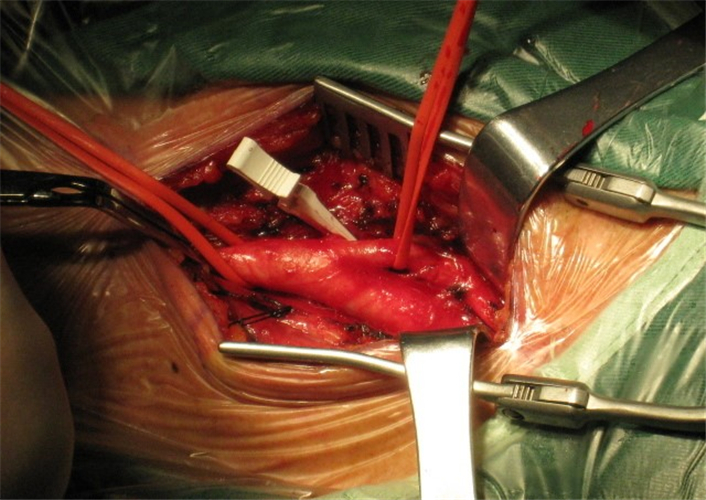

手術治療頸動脈狹窄腦供血不足